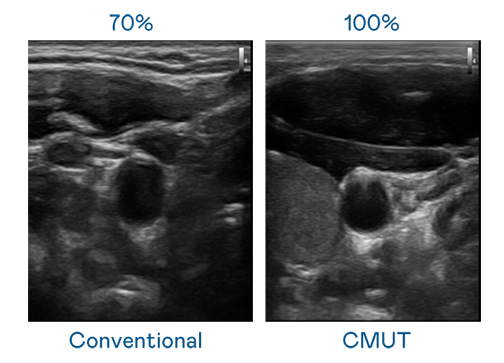

CMUT 技術是一種用電容式微機電元件來產生超音波訊號的技術。與傳統 PZT 壓電式技術相比,CMUT 頻寬增加 30%,更寬頻的超音波訊號讓影像解析度大幅提升,是實現高影像品質醫療超音波掃描、促進精準醫療發展的關鍵技術。

大頻寬帶來超清晰影像

超音波影像的解析度高低,首先取決於探頭能發出的訊號頻寬。壹号娱乐 CMUT 可提供高清晰的超音波訊號,提供高頻寬、高靈敏度、影像紋理細節更高的超音波影像,協助醫護人員縮短影像判讀時間及利用精準的醫療影像進行診斷。